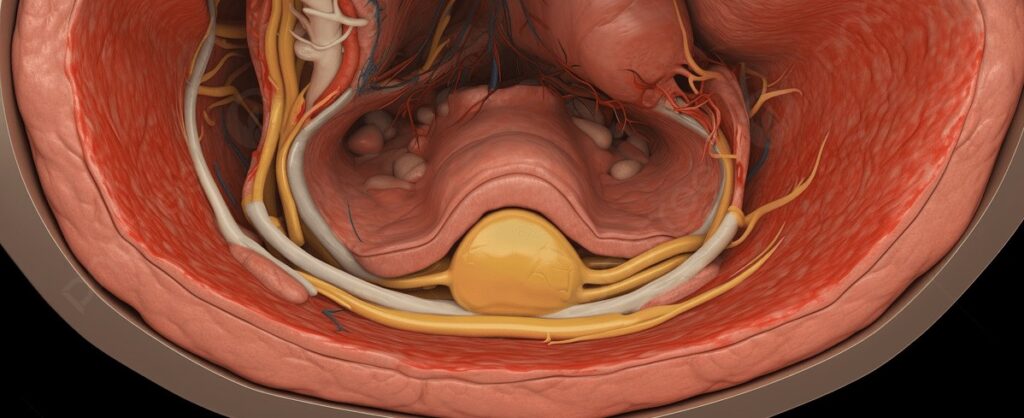

De voornaamste oorzaak van maagklachten in onze moderne samenleving is stress. De nervus vagus is de zenuwbaan die je hersenen verbindt met je maag en alvleesklier.

Onze pancreas geeft zijn sappen af via de sphincter van Oddi, een kleine spier die opent en sluit. Bij stress of een tekort aan magnesium kan deze spier zich samentrekken, waardoor de sappen niet goed doorstromen.